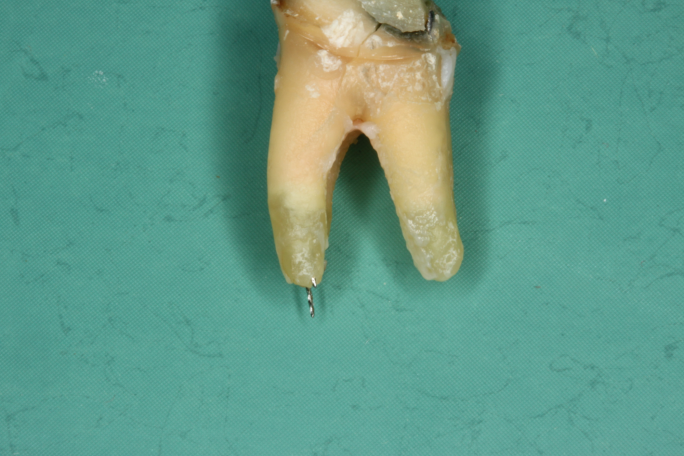

Wurzelkanalbehandelte Zähne sind tote Zähne! Auch die beste Mikro-Endodontie wird kaum eine komplett bakteriendicht abgeschlossene Wurzel realisieren können. Akzessorische Seitenkanäle und die Endo-Paro Verbindung über die Dentintubuli bleiben bestehen.

Technische Limitation

Pro Quadratmillimeter Wurzeldentin befinden sich 40 bis 60 tausend Dentinkanälchen, welche sich dann auf eine Länge von etwa 1 – 5 km summieren.